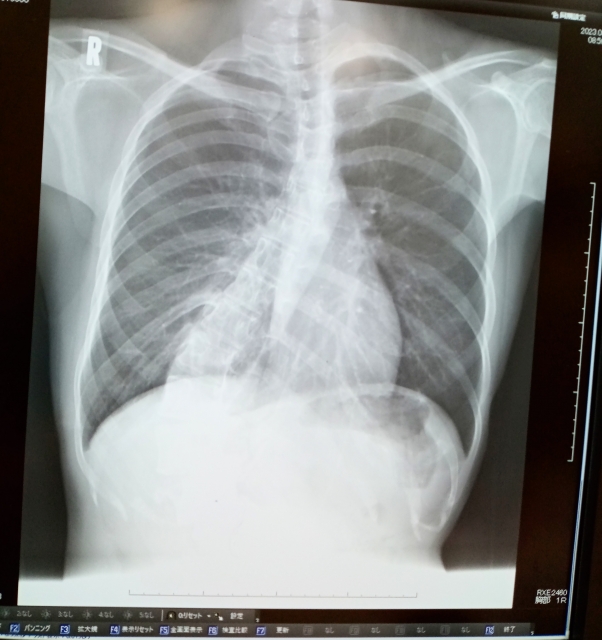

側弯症は、背骨が正常な直線状態から逸脱し、横向きに曲がる医学的状態を指します。この病状は、背骨の曲がりが10度以上ある場合に側弯症と診断され、主にX線画像を用いて確認されます。

側弯症の診断には、まず医師が患者の背中を視覚的に検査し、肩や腰の高さの非対称性を確認します。その後、X線検査が行われ、背骨の曲がり具合を正確に測定します。このX線画像を用いて、側弯症の程度を示すコブ角(Cobb角)が計測され、診断に重要な役割を果たします。必要に応じて、MRIなどのさらに詳細な画像診断が行われることもあります。

画像診断は側弯症の診断と評価に不可欠です。X線検査は、背骨の曲がり具合を詳細に確認し、側弯症の程度を定量的に評価するために広く用いられます。この検査により、コブ角(Cobb角)が測定され、側弯症の重症度が定義されます。

一方、MRI検査は、背骨や周囲の組織の詳細な画像を提供し、側弯症の原因が神経系の異常に関連している場合に特に有用です。MRIは、脊髄や神経根の圧迫、脊髄異常など、X線では捉えられない詳細を明らかにすることができます。これらの画像診断技術は、側弯症の正確な診断、治療計画の策定、および治療の効果をモニタリングするために重要な役割を果たします。